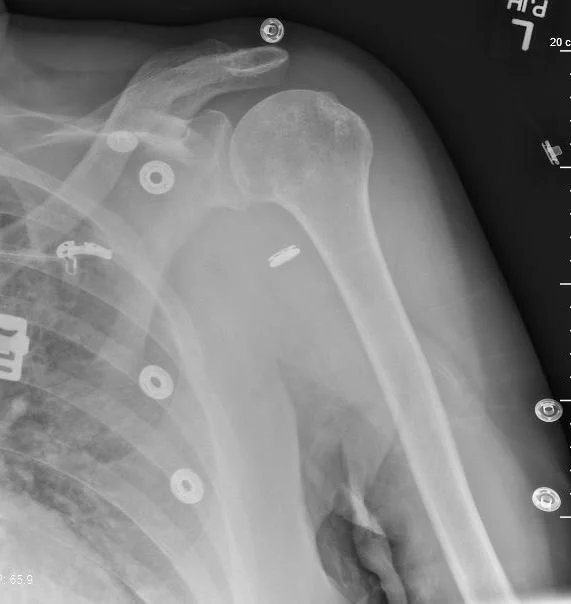

A 69 y.o. woman sustained a shoulder dislocation after a mechanical fall. It was relocated at an outside hospital

Now she is unable to move he arm and complains of numbness from the midhumerus distally. What happened?

this is the post reduction film.